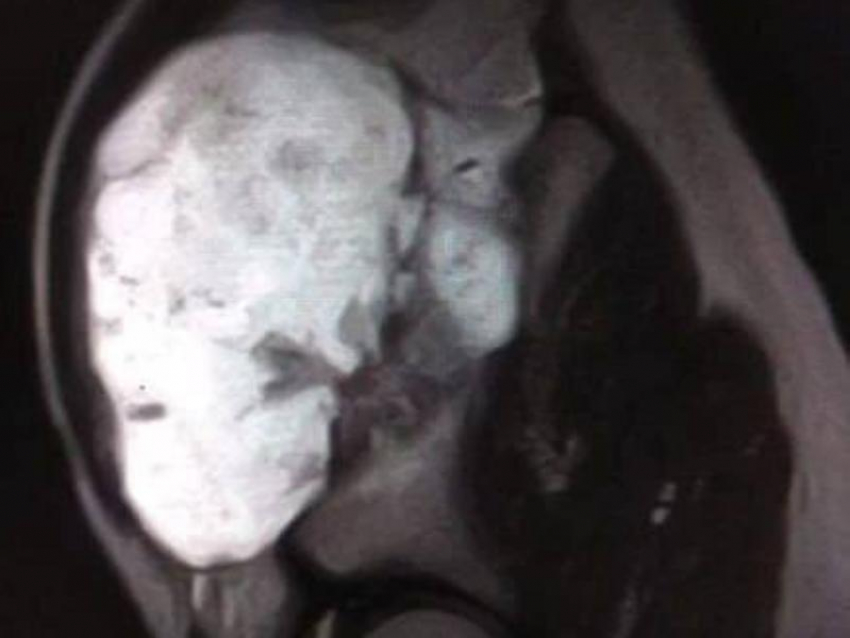

В Воронеже врачи областной детской клинической больницы №2 провели сложную операцию 13-летнему мальчику с крупным костным образованием.

Юный пациент обратился к медикам с жалобами на дискомфорт и ограничение подвижности. При обследовании специалисты обнаружили внушительный нарост на кости размером 12×9×7 сантиметров. По словам врачей, образование не только мешало нормально двигаться, но и представляло серьёзную угрозу – при дальнейшем росте оно могло повредить тазобедренный сустав и привести к осложнениям.